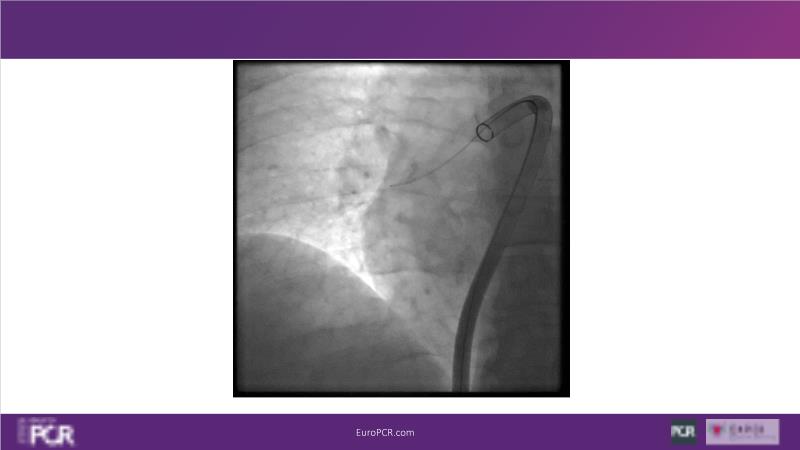

Why mechanical thrombectomy should be considered in the management of acute pulmonary embolism

In this EuroPCR 2024 session, study the case of a patient with high-risk pulmonary embolism and another with intermediate to high-risk pulmonary embolism, delve into discussions on clinical evidence for mechanical thrombectomy in pulmonary embolism, acquire skills to evaluate eligibility for mechanical thrombectomy, and learn how to integrate such technique in local pulmonary embolism patient pathway.